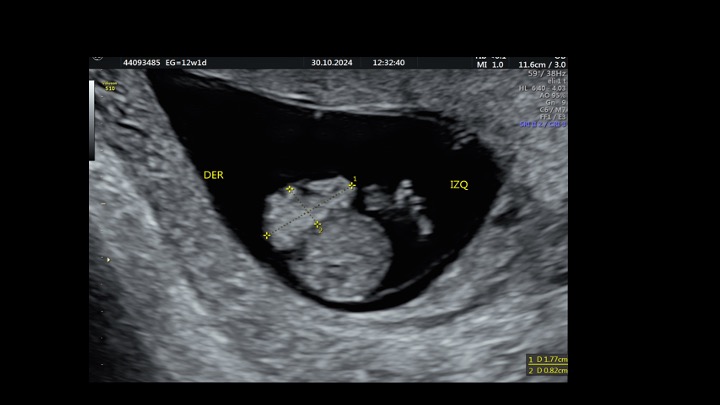

Se presenta el caso de una paciente de 23 años de edad, secundigesta, sin antecedentes personales ni familiares de relevancia. La paciente adjunta el estudio de screening de aneuploidías de la semana 11-14, que arroja bajo riesgo. Las imágenes 1 y 2 describen los hallazgos identificados durante la evaluación de la anatomía fetal en la semana 12. Las imágenes 3, 4 y 5 corresponden a los controles ecográficos posteriores, del segundo y tercer trimestre. La imagen 6 muestra al recién nacido. Seleccione la opción correcta: A. Corresponde a una hernia umbilical fisiológica con resolución más tardía. B. Corresponde a una gastrosquisis con cierre espontáneo intraútero. C. Corresponde a un onfalocele con ruptura del mismo. D. El defecto de pared cerró espontáneamente mejorando el pronóstico y riesgo de complicaciones gastrointestinales. Figura 1: se visualiza corte axial del abdomen fetal, a nivel de la inserción del cordón umbilical, con Doppler color en semana 12. Figura 2: se observa corte axial, a nivel de la inserción del cordón umbilical en la pared abdominal anterior, en semana 12. Figura 3: corte sagital a nivel de la inserción del cordón en la pared abdominal anterior, con Doppler color, en semana 20. Figura 4: corte axial del abdomen fetal, en semana 32, donde se identifica dilatación de las asas intestinales. Figura 5: corte axial del abdomen fetal, en semana 32, donde se identifica dilatación de las asas intestinales, con la utilización del Doppler color. Figura 6: se observa al recién nacido.

El caso presentado corresponde a una paciente de 23 años, secundigesta, sin antecedentes personales de relevancia, con embarazo único y espontáneo, que concurre al consultorio de ecografía para realizar un screening combinado del primer trimestre en la semana 12. Se evidencia solución de continuidad en la pared abdominal anterior, adyacente al cordón umbilical, con exteriorización de asas intestinales, compatible con gastrosquisis (Figuras 1 y 2).